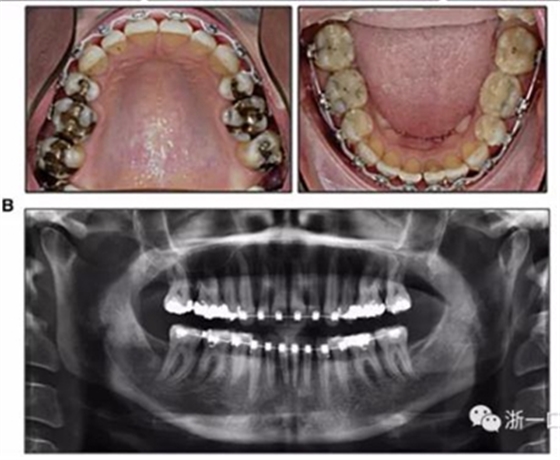

擴弓保持8周后,除擴弓器影響牙外粘接托槽,使用0.014鎳鈦絲進行排齊、整平。旋轉(zhuǎn)停止后3個月拆除擴弓器,全口粘接托槽,使用0.016niti繼續(xù)排齊整平。佩戴可摘保持器,保持上頜寬度。在使用至0.018x0.018niti7周,徹底排齊整平后,使用大弓型的0.016x0.022不銹鋼絲,繼續(xù)維持原有寬度,同時停止使用可摘保持器。掛II類牽,糾正磨牙關(guān)系,使用鏈圈關(guān)閉散在間隙,少量使用IPR去除局部前牙的黑三角。術(shù)后9個月拍全景示,牙根平行度可,再無其他牙根出現(xiàn)問題。1年7個月后治療結(jié)束。上下頜3-3舌側(cè)保持器+哈雷氏保持器進行保持。

患者側(cè)貌改善,下唇唇肌緊張消失,上下唇可自然閉合。磨牙及尖牙關(guān)系糾正至I類,覆合覆蓋正常。上下頜弓型糾正至卵圓形,牙弓寬度增加。頭影測量分析示SNA角81.8°,ANB角3°。頭影測量重疊圖示下頜骨向后旋轉(zhuǎn),垂直面高度略有增加。

19個月后復(fù)查,情況穩(wěn)定,牙弓寬度穩(wěn)定。